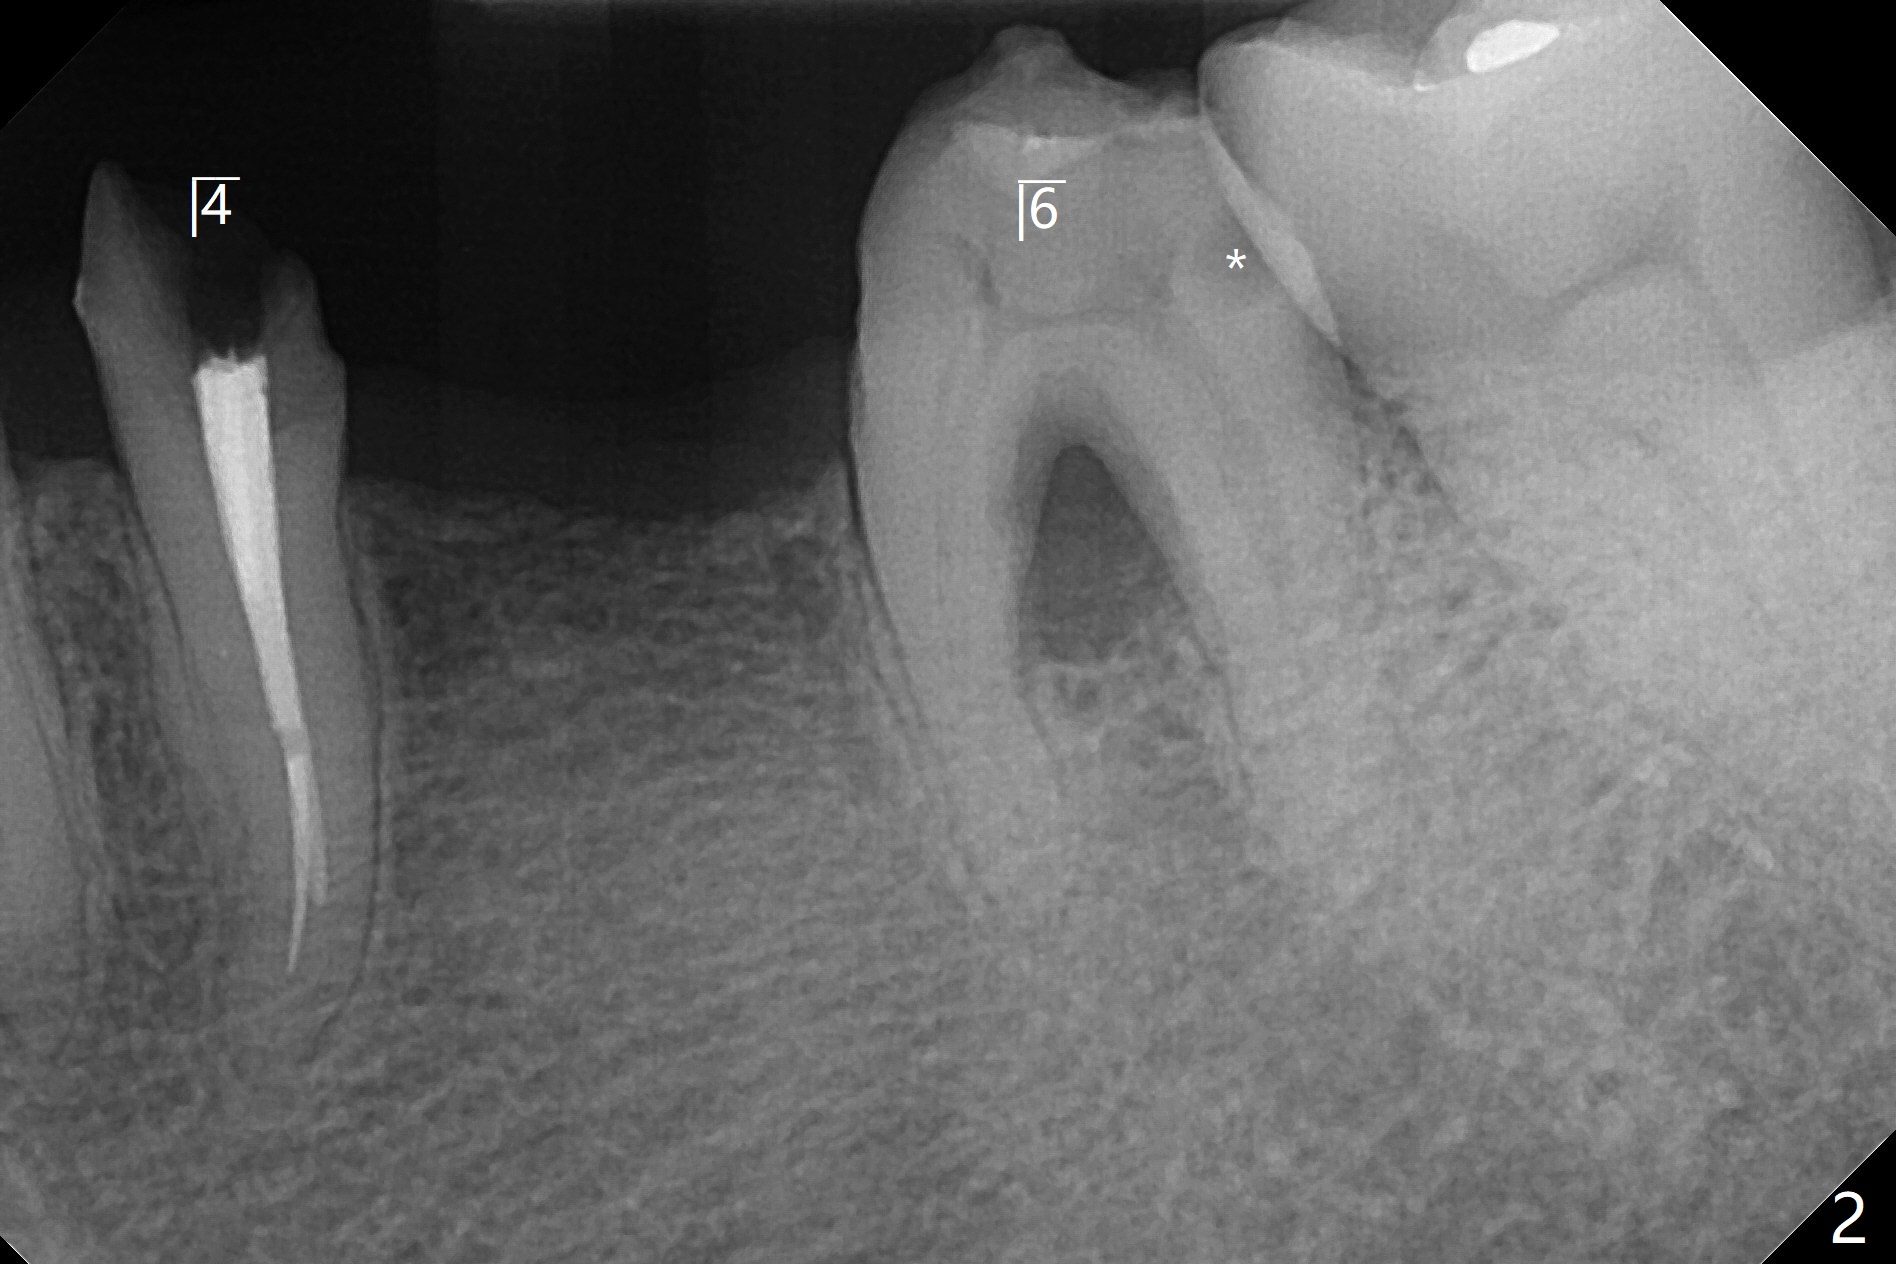

63岁女对肾上腺素和90%以上抗生素过敏,左上5(短根,巨大根尖阴影,图一),左下6(根分叉感染,远中龋齿(图二:*),左下4(牙齿断裂略微龈下:图二,五)似乎很难保留,左下5骨质宽度,高度也允许植牙(图四)。由于左上5需要提升术,可能出现上颌窦感染,Z Pack是否引起过敏反应不确定,拔牙植骨与提升植牙分期做(术前拍摄根尖片)。而下颌一期完成。